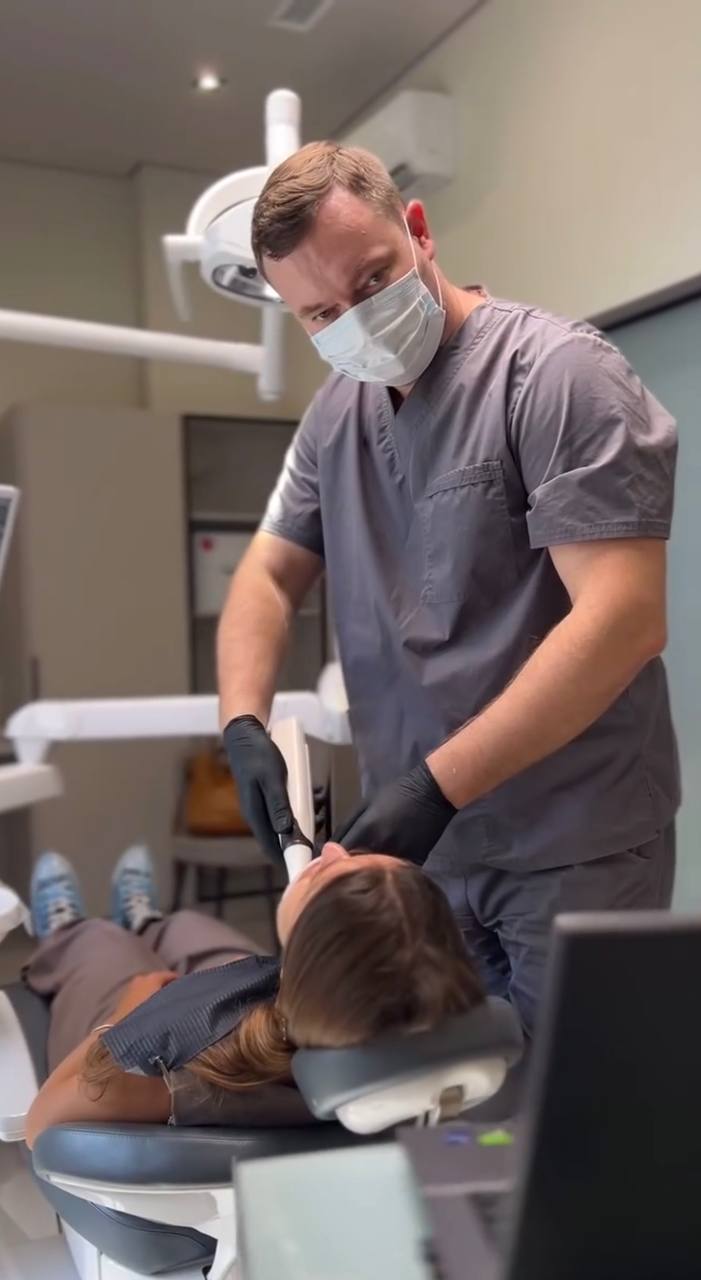

Мене звати Андрій Малюкін. Разом із дружиною Ольгою ми відкрили цю затишну стоматологію в Одесі, щоб лікувати пацієнтів як своїх рідних. Ми поєднуємо традиційні методи та найновіші цифрові технології для вашої ідеальної усмішки.

Ми — не мережева клініка і не конвеєр. У нас лише два кабінети, бо для нас важлива не кількість, а увага до кожної людини. Ми знаємо наших пацієнтів по імені, пам’ятаємо їхні історії й завжди раді зустрічі.

Саме тому я, як головний лікар, особисто супроводжую кожен план лікування, щоб ви були впевнені у результаті.

"Наша філософія дуже проста: ми зберігаємо те, що можна зберегти, і пропонуємо лише те, що справді потрібно."